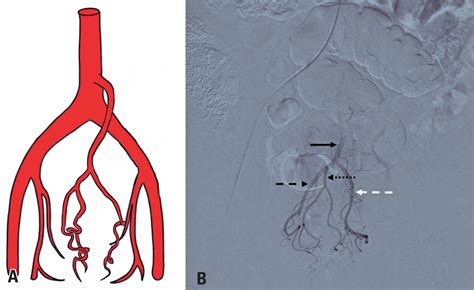

Hemorrhoid Artery Embolization is a cutting-edge, image-guided procedure performed by interventional radiologists. Unlike traditional surgery, which physically removes the hemorrhoidal tissue, HAE works by targeting the blood supply that feeds the hemorrhoids. By reducing the arterial blood flow to the hemorrhoidal plexus, the procedure causes the hemorrhoids to shrink over time, effectively alleviating symptoms like bleeding, pain, and protrusion.

Because it is a minimally invasive technique, it does not require general anesthesia or incisions in the sensitive anal region. Instead, a tiny catheter is guided through a blood vessel in the wrist or groin to the specific arteries supplying the hemorrhoids. Small particles are then injected to block these vessels, successfully reducing the pressure and engorgement of the hemorrhoidal tissues.

2. Guidance: Using real-time X-ray imaging (fluoroscopy), the radiologist navigates a microcatheter through the vascular system.

3. Embolization: Once the specific hemorrhoidal arteries are identified, specialized embolic agents are injected to reduce the blood supply.